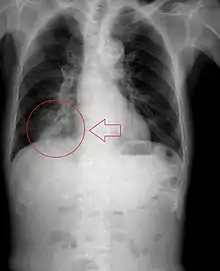

![]() | |

Upper gastrointestinal series at the level of the esophagus, showing pulmonary aspiration of the radiocontrast agent | |